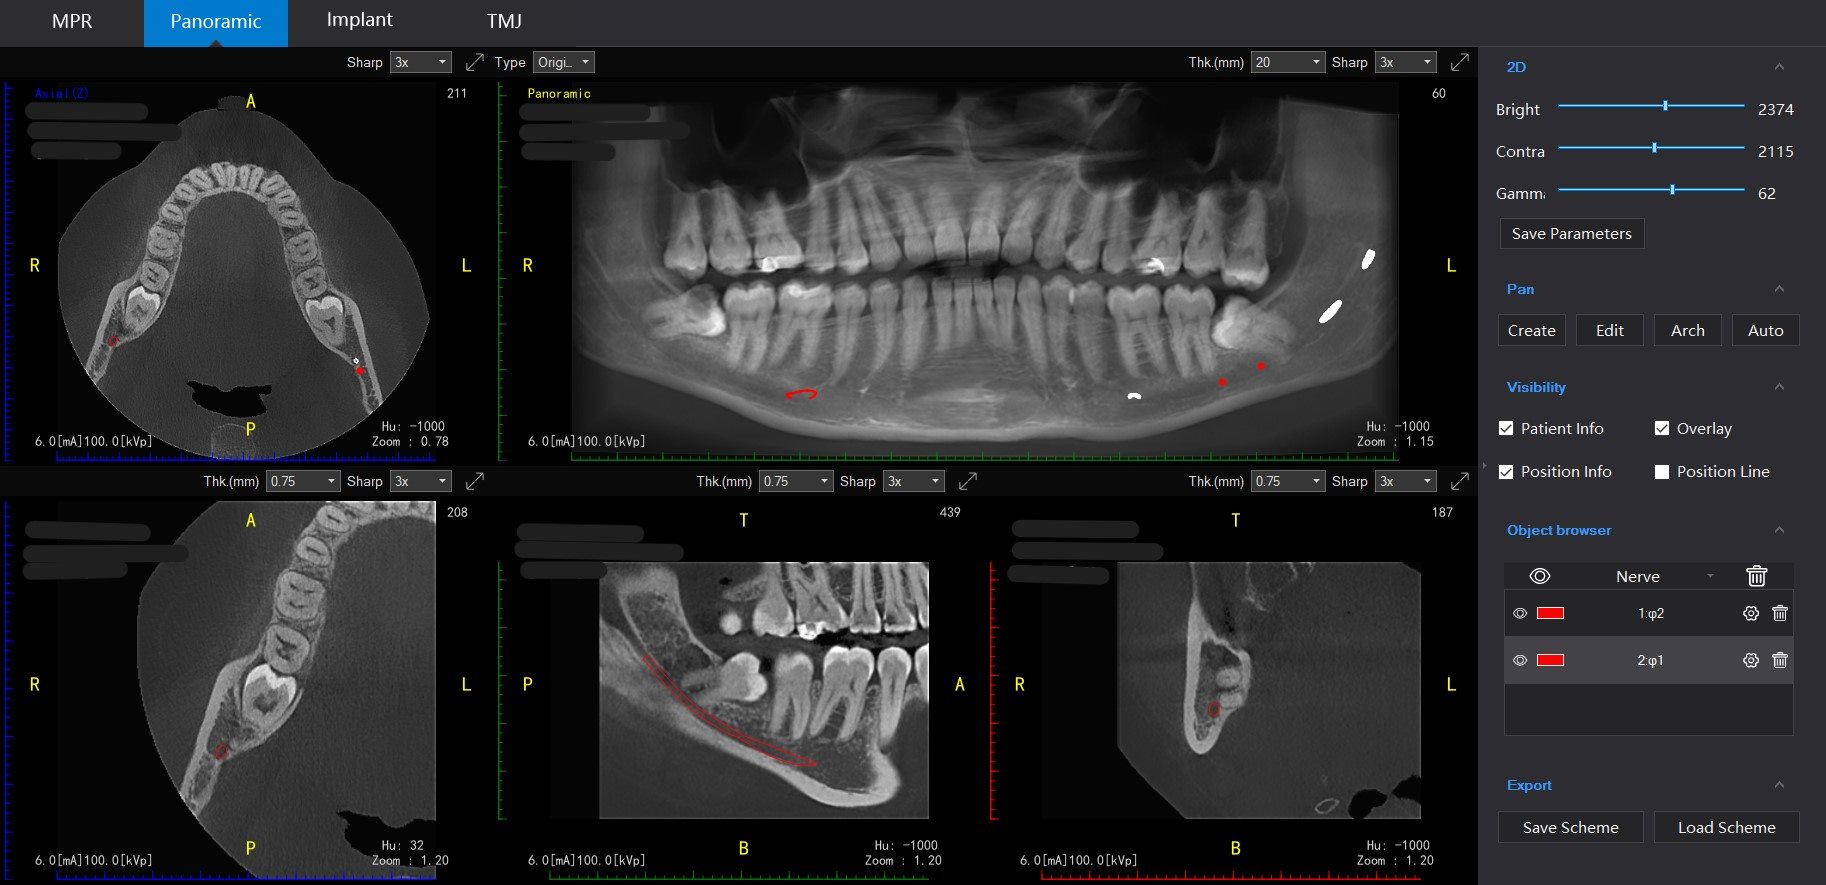

Before undergoing wisdom tooth surgery, a thorough evaluation and diagnosis are essential. X-rays and clinical examinations are conducted to determine the position of the wisdom teeth, their impact on surrounding teeth, and the best approach for extraction.